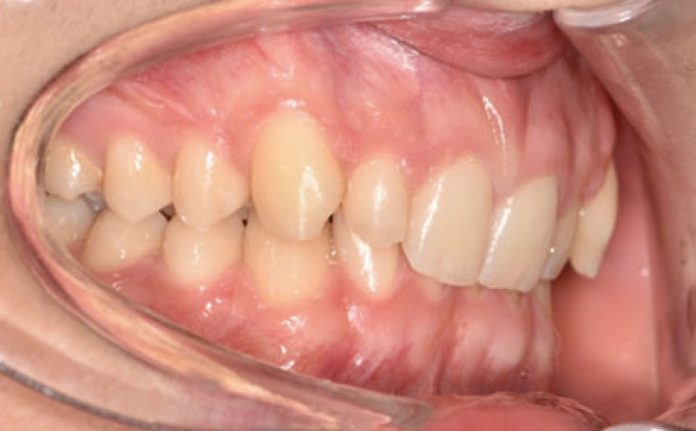

Il paziente si è presentato per la sua prima visita presso il reparto di Odontoiatria e Protesi Dentaria dell’Ospedale Vita-Salute San Raffaele diretto dal prof. E. F. Gherlone. All’esame obiettivo era evidente una malocclusione scheletrica e dentale di classe II associata a morso profondo e lieve affollamento anteriore superiore. In particolare, sono stati segnalati: rapporti occlusali di classe II, morso profondo, perdita di overjet, contrazione dell’arcata superiore e inferiore con leggero affollamento (fig. 1a-f). La richiesta del paziente era quella di migliorare l’estetica dei denti anteriori con allineatori invisibili di tipo Invisalign. Tuttavia, sia il paziente che il genitore sono stati informati che, per ragioni di efficacia e risoluzione del problema, era necessario agire anche a livello di funzionalità e risoluzione della malocclusione.

Infatti, durante il primo controllo due mesi dopo, è stato osservato un miglioramento della classe molare (fig. 3a-c).

Un mese dopo, durante il secondo controllo, è stata raggiunta la posizione dei molari richiesta e, di conseguenza, il Carriere Motion è stato sospeso e si è iniziato il trattamento di ortodonzia fissa (fig. 4a-c).

Nello specifico, sono stati eseguiti bandaggi superiori e inferiori con tecnica Damon per l’allineamento e il livellamento delle arcate dentarie con l’aggiunta di rialzi occlusali, al fine di aprire il morso, ed elastici di classe II a tempo pieno (fig. 5a-c).